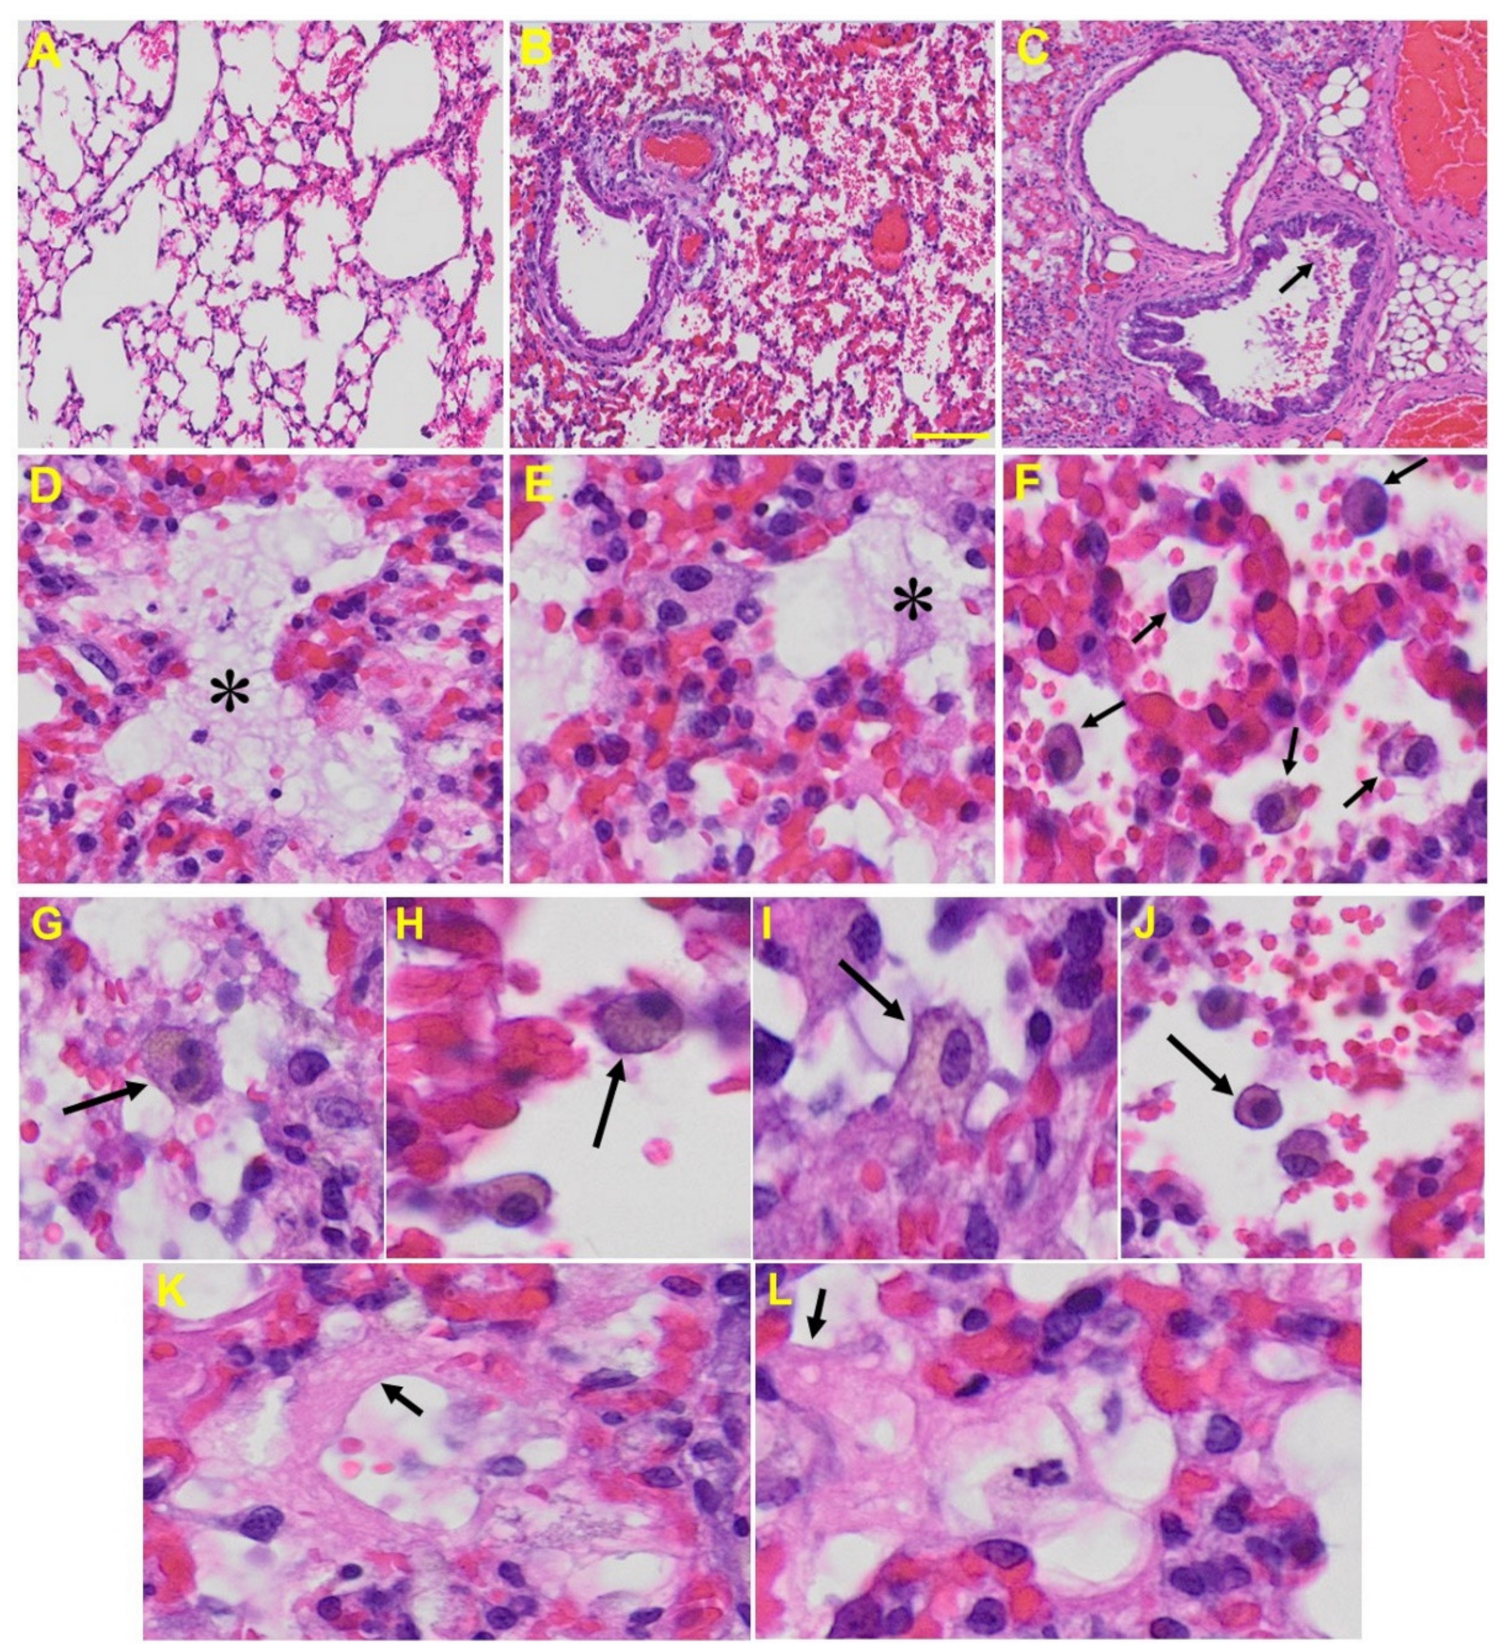

Lung: MHV-1-infected mice at day 7 showed inflammation (i.e., granular degeneration of cells, and migration of leukocytes into the lungs), along with proteinaceous debris filling of the alveolar spaces with fibrillar to granular eosinophilic protein strands caused by the progressive breakdown of the capillary wall and epithelial integrity, permitting leakage of protein rich edematous fluid into the alveoli, and the presence of hemosiderin-laden macrophages (indicating pulmonary congestion with dilated capillaries and leakage of blood into alveolar spaces). Furthermore, peribronchiolar interstitial infiltration, bronchiole epithelial cell necrosis, necrotic cell debris within alveolar lumens, alveolar exudation, hyaline membrane formation, alveolar hemorrhage with red blood cells within the alveolar space, and interstitial edema are all characteristic features of infected lungs in humans with SARS-CoV-2 infection [64] (Figure 5).

Figure 5.

Lung from MHV-1 exposed mice. (A) Normal mouse. (B) MHV-1-infected mouse lung at day 7. (C) The MHV-1 infected mouse lung shows inflammation, granular degeneration of cells, and migration of leukocytes into the lungs (arrow). (D,E) Proteinaceous debris filling of the alveolar spaces with fibrillar to granular eosinophilic protein strands caused by progressive breakdown of the capillary wall and epithelial integrity, permitting the leakage of protein-rich edema fluid into the alveoli (asterisk) (commonly seen in ARDS). (F–J) Presence of hemosiderin-laden macrophages, indicating pulmonary congestion with dilated capillaries and leakage of blood into alveolar spaces. Further, peribronchiolar interstitial infiltration, bronchiole epithelial cell necrosis, necrotic cell debris within alveolar lumens, alveolar exudation, infiltration, hyaline membrane formation (K,L), and alveolar hemorrhage with red blood cells within the alveolar space and interstitial edema were also observed in these mice (H&E original magnification 400× Figure 5A–C; scale bar image divided by actual scale bar length).

It should be highlighted that the above-mentioned changes were recapitulated in MHV-1 infection in mice. More precisely, proteinaceous debris filling the alveolar spaces with fibrillar to granular eosinophilic protein strands was observed. This may have been caused by progressive breakdown of capillary walls and epithelial integrity, which permits the leakage of protein rich edema fluid into the alveoli—events commonly seen in ARDS [83]. This proteinaceous fluid presents itself as a lightly eosinophilic material that ranges from homogenous to fibrillar (i.e., fibrin strands). Furthermore, the presence of hemosiderin-laden macrophages, an iron storage complex that is composed of partially digested ferritin and lysosomes, was seen frequently, indicative of pulmonary congestion with dilated capillaries and leakage of blood into alveolar spaces. The breakdown of heme gives rise to biliverdin and iron. The body then traps the released iron and stores it as hemosiderin in tissues. Hemosiderin is also generated from the abnormal metabolic pathway of ferritin [84]. Our findings collectively suggest major defects in the lung of MHV-1 infected mice, similar to those observed in humans in association with SARS-CoV-2 infection.